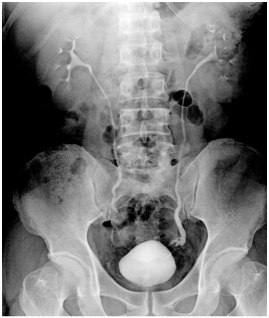

On the 21st postoperativeday, she was presented again with fever and the symptoms of peritonitis and bilateral flank pain. Transvaginal sonography revealed fluid in the Douglas pouche. A culdocentesis was performed and the fluid was reported containing high urea (107mg/dL) and high creatinin (6.4mg/dL). A new IVP showed extravasation of contrast dye in the lowerpart of the left ureter (Figure 1). She transferred to urology department and underwent cystoscopic double-J stenting. Ten days of stenting did not lead to healing. On the 31st postoperative day, she underwent ureteroneocystostomy operation. Ureteral catheter was removed at the sixth postoperative week. Imaging at the third postoperative month was normal.

Figure 1 Pyelogram showing the leakage in the left ureter distalend.